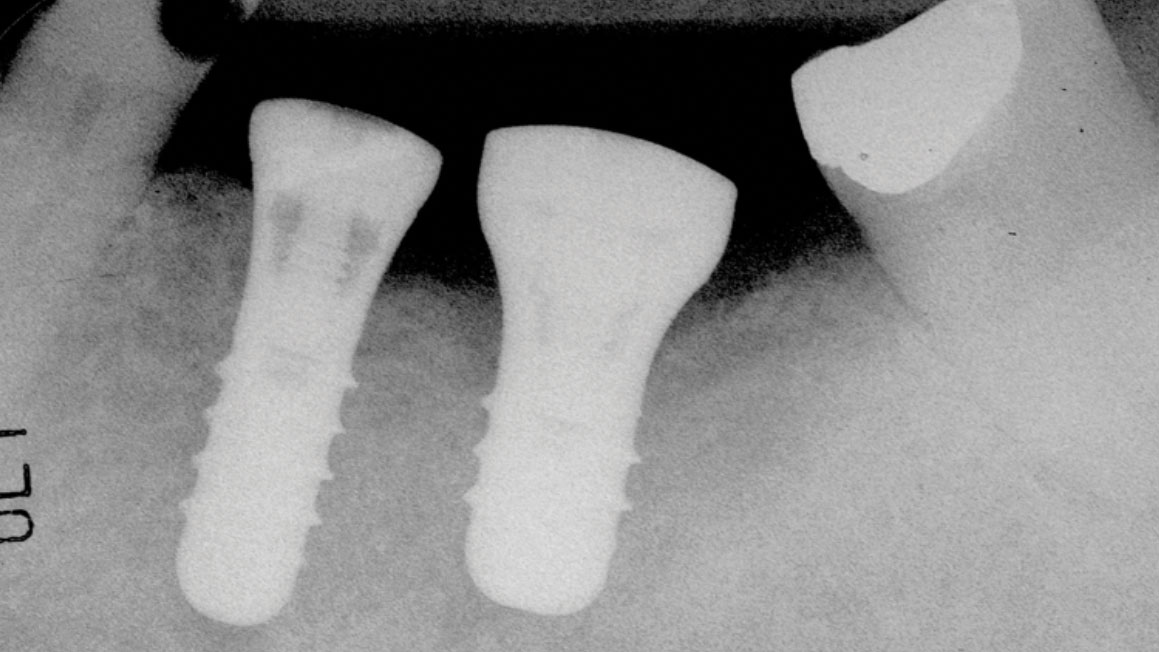

Silent progression: Full-arch implant peri-implantitis after 25 years without maintenance

Abstract Background: Peri-implantitis is a serious complication for both patients and clinicians. Affected implants typically show extensive bone loss in radiographs, are difficult to manage and usually lead to implant loss leaving significant alveolar bone defects. Methods: In 2009 the patient reported here received two endosseous implants to replace his mandibular left second bicuspid and first molar … Read more